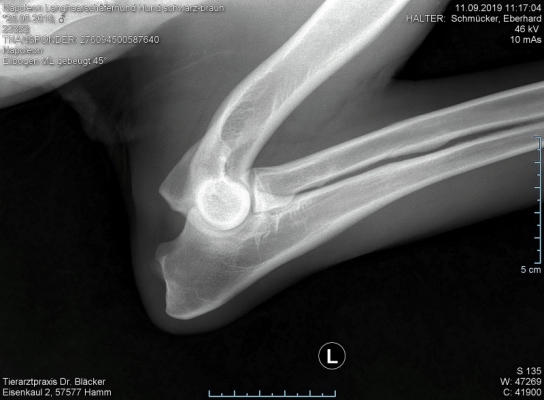

Röntgentermin am 11.09.2019

Hier sind  HD-ED Aufnahmen von unseren “Napoleon von KaTum”   alles Top

Keine HD und kein ED,LÜW ist alles gut